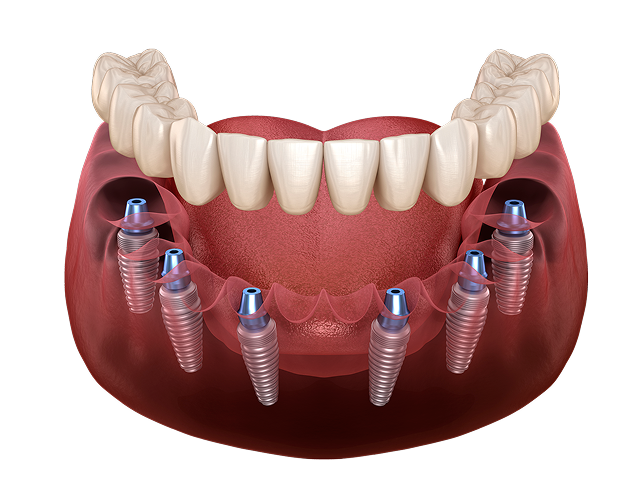

6 имплантов

• Оптимальное количество имплантов

• Хорошая стабильность протеза

• Без костной пластики

Стоимость под ключ 400 000 ₽